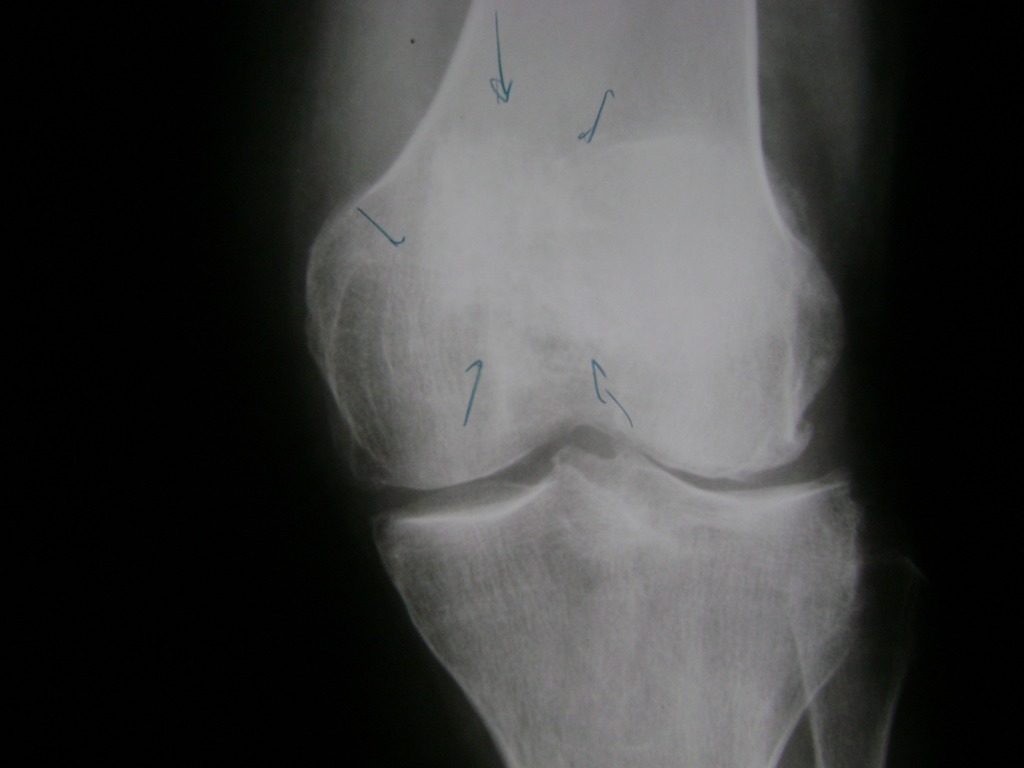

Húmero - Rodilla